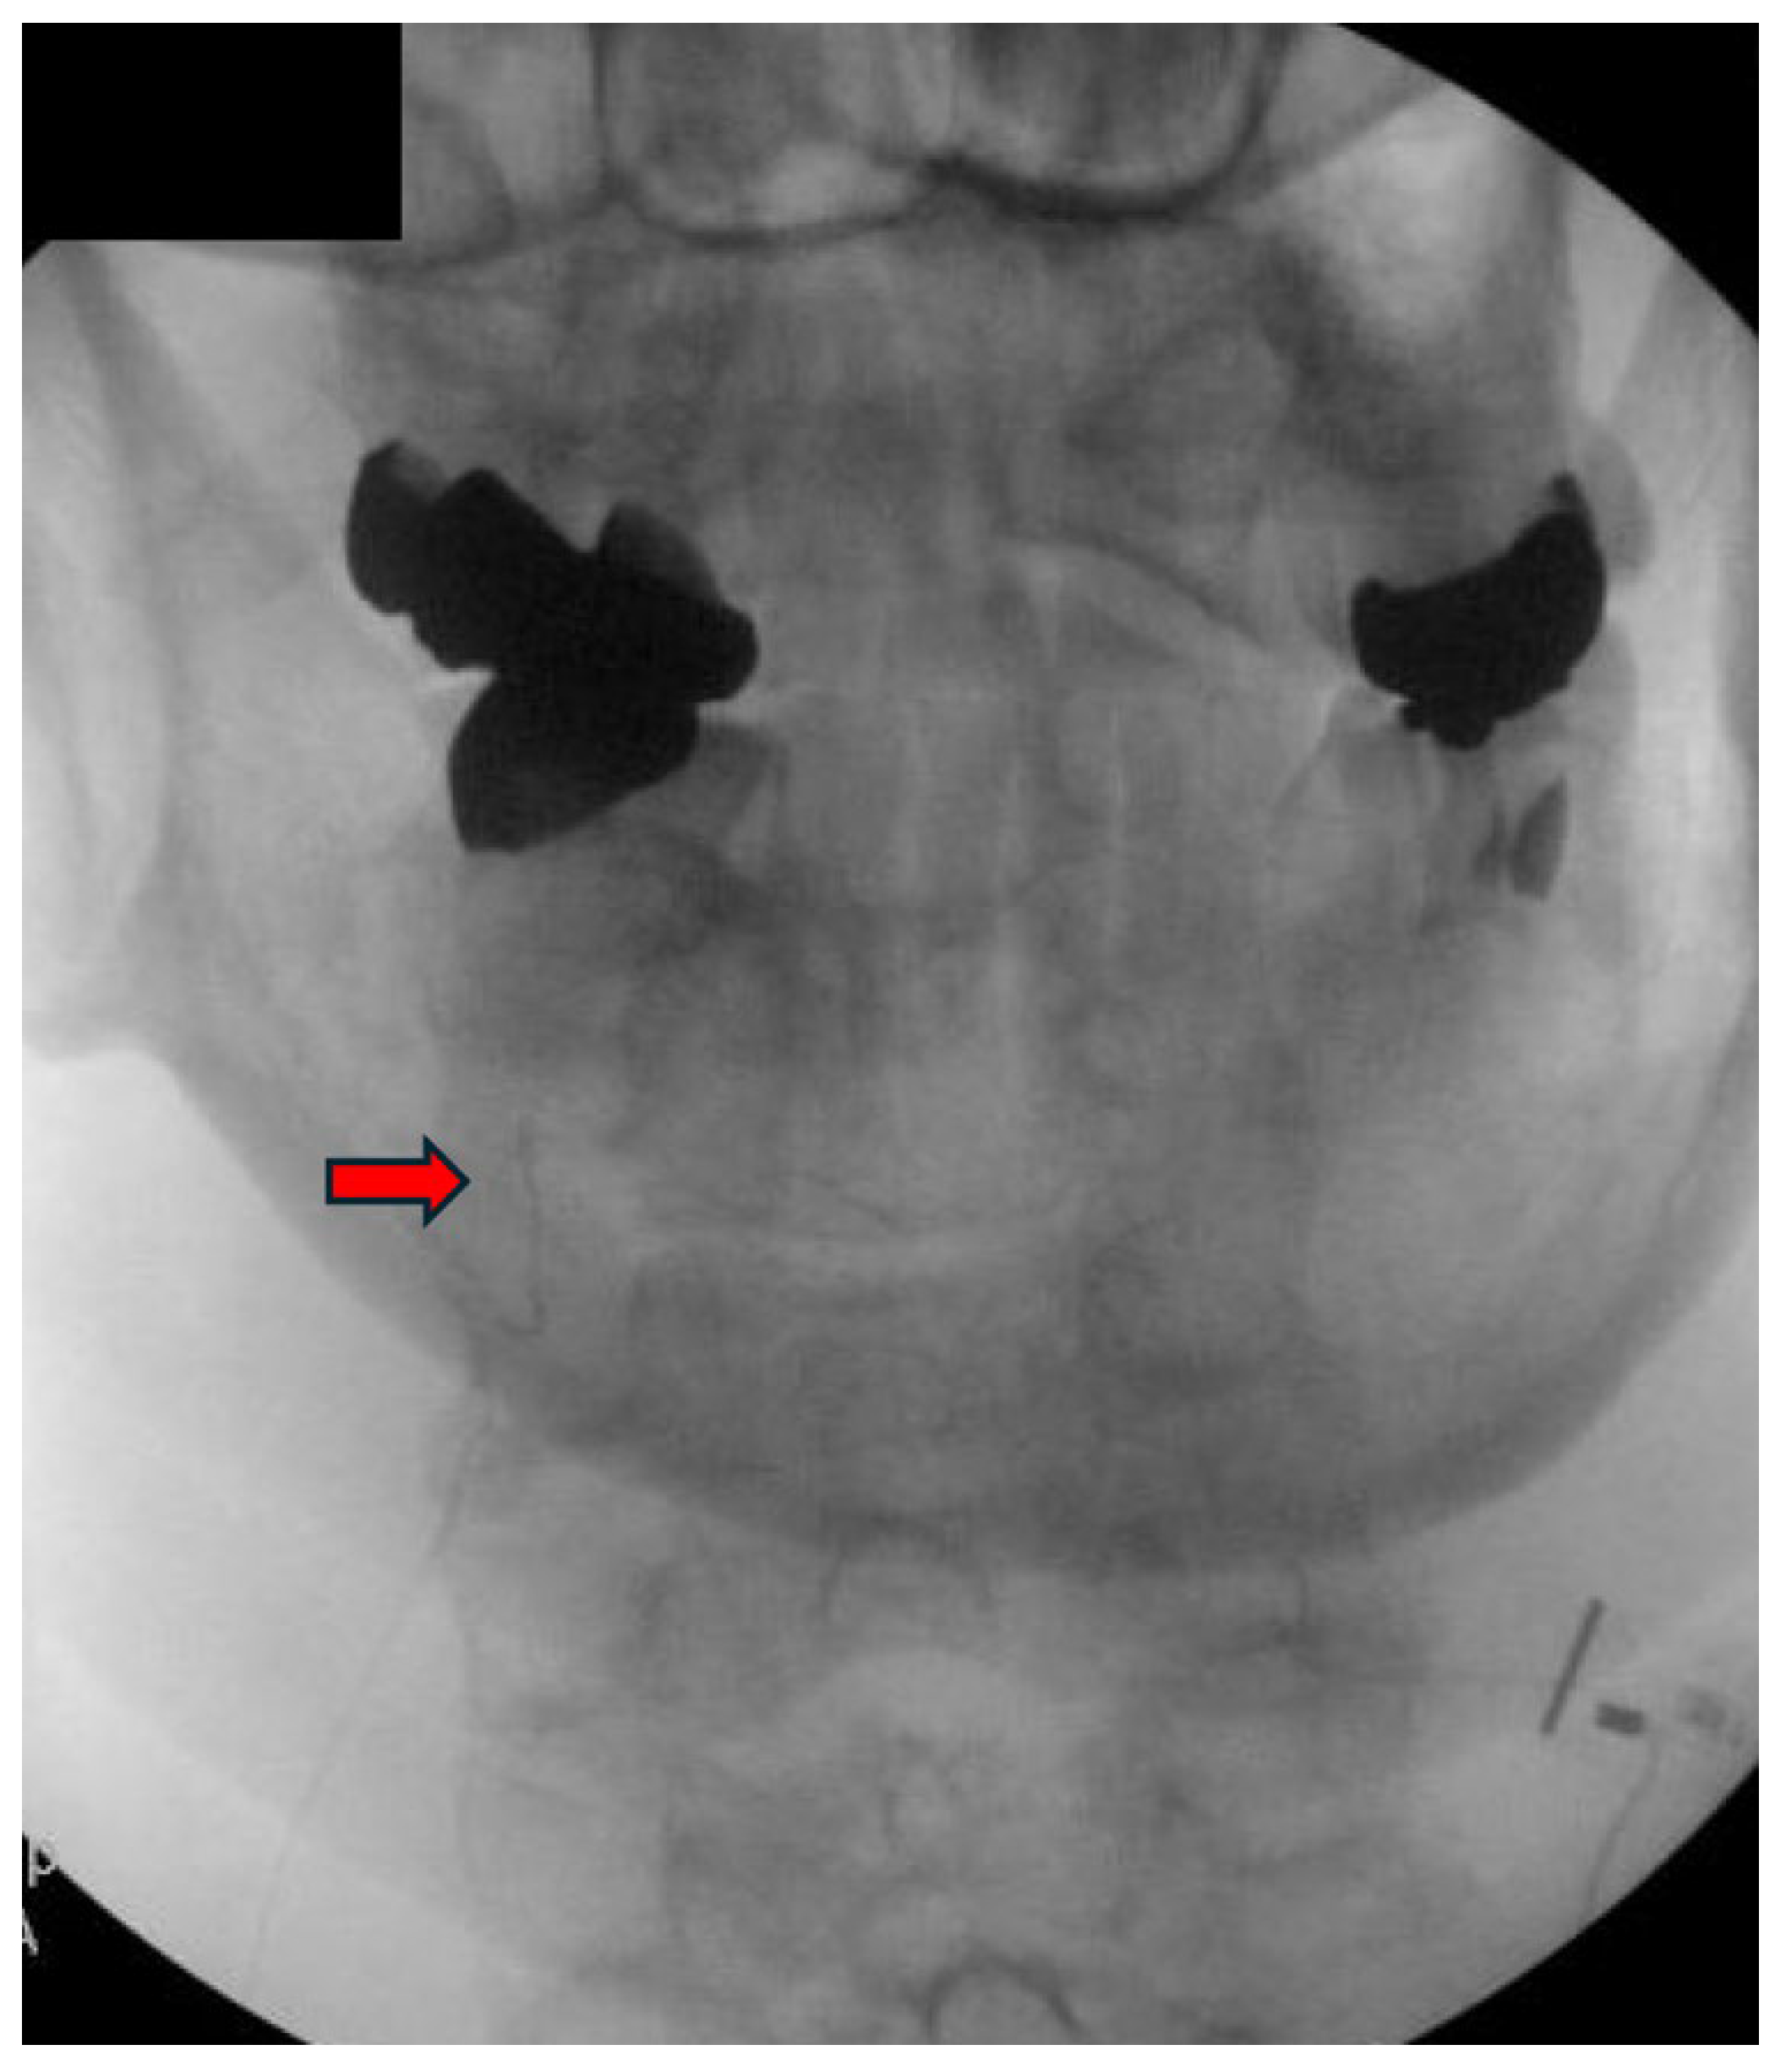

3.3. Procedure Description